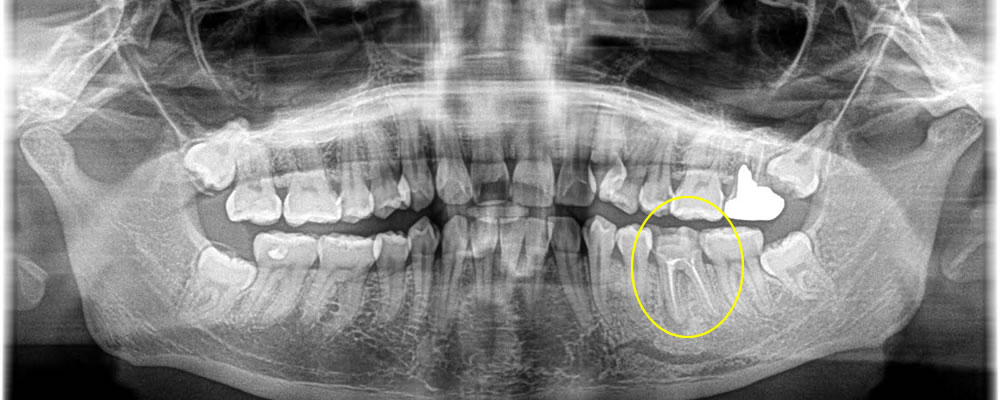

こちらの患者さまは左下の歯が痛く、他院にて抜歯を勧められたとのことでインプラント治療希望にて来院されました。

まずCT検査を行い、歯の周りの感染状況をチェックし、保存困難な事を確認しました。その後、治療法のカウンセリングを行い、やはりインプラント治療を行いたいとの事で治療を開始しました。